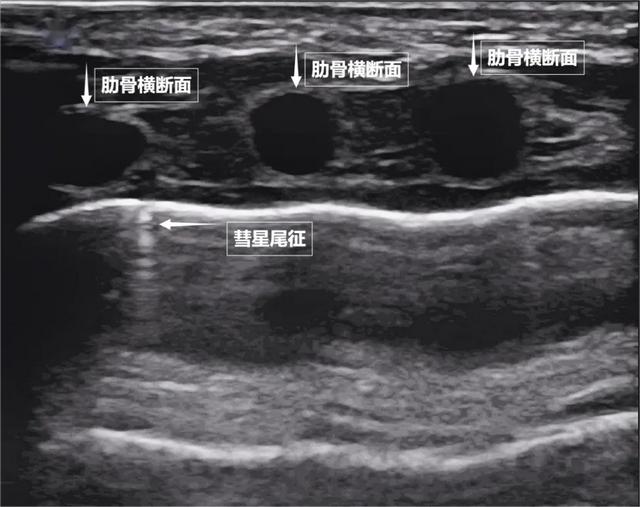

图为正常新生儿肺部超声表现第二景:“沙滩与浪花”——肺滑动征如果我们把超声图像调成实时动态模式,把“照片”变成“电影”,更神奇的一幕出现了。随着呼吸,胸膜线会随胸廓运动轻柔滑动,这就是“肺滑动征”。它意味着肺与胸壁正紧密相依、自由顺畅地呼吸。若肺与胸壁间有气胸或胸腔积液,这种滑动会消失。有时,在胸膜线下方还会出现细小的亮白色闪烁点,称为“彗星尾征”(见下图)。其少量、孤立出现时,通常是正常肺小叶间隔的反射,无需担心。